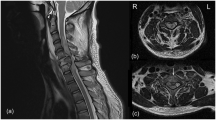

Given the superior mechanical properties and significant neuroprotection of PLCL5MS, and the better neuroprotective effect and mechanical properties of PLCL10MS compared to pure PLCL, PLCL5MS and PLCL10MS wires were selected as stent implant alternatives for further in vivo experiments using tMCAO rat models, with pure PLCL wires serving as the control group (Fig. 7A). All in vivo neurological analyses were conducted by implanting PLCLxMS wires into the tMCAO models.

A Schematic diagram of stent strut implantation process. B Brain slices stained with TTC to differentiate between healthy tissue (red) and damaged tissue (white). C Quantification of brain infarct volume from (B). D, E Brain slices with Nissl staining and quantification of Nissl bodies; scale bars: 1 mm and 25 µm. F Evaluation of brain water content ratio. G Representative Evans blue extravasation image illustrating blood-brain barrier disruption. H Quantification of cerebral Evans blue content. I Measurements of CBF before, during, and after surgery. J Comparison of relative CBF across groups. Source data and exact P values are provided as a Source data file. Two-way analysis of variance (ANOVA) with a Tukey/Games-Howell post hoc test for multiple comparisons. Sample size: n = 6 biologically independent replicates. *P < 0.05, **P < 0.01, ***P < 0.001, tMCAO+PLCL5MS or tMCAO+PLCL10MS vs. tMCAO group; # P < 0.05, ## P < 0.01, ### P < 0.001, c or tMCAO+PLCL10MS vs. tMCAO+PLCL group; §P < 0.05, §§ P < 0.01, §§§ P < 0.001, tMCAO+PLCL10MS vs. tMCAO+PLCL5MS. Data are presented as mean values ± SD.

The tMCAO group exhibited significant infarct injury, and pure PLCL wire implantation had no effect on the infarction area. However, the tMCAO+PLCL5MS and tMCAO+PLCL10MS groups could reduce the infarction area, with the tMCAO+PLCL10MS group exhibiting the smallest infarction area (Fig. 7B, C). Moreover, the results of Nissl staining were consistent with triphenyl tetrazolium chloride (TTC) staining. The tMCAO group suffered severe neural damage in the cortex and striatum, which could not be mitigated by pure PLCL wire implantation. In contrast, PLCL5MS and PLCL10MS wire implantations inhibited neural damage, especially in the PLCL10MS group, which displayed more healthy neurons in the striatum than the PLCL5MS group (Fig. 7D, E). Furthermore, the blood-brain barrier (BBB) in the tMCAO group and tMCAO+PLCL group underwent severe damage, leading to pronounced brain edema and Evans blue extravasation. However, the BBB function in the tMCAO+PLCL5MS and tMCAO+PLCL10MS groups was more intact, particularly in the tMCAO+PLCL10MS groups (Fig. 7F–H). Additionally, relative cerebral blood flow (CBF) was measured. On the first day after reperfusion, both the PLCL5MS and PLCL10MS groups showed better CBF recovery than the tMCAO and tMCAO+PLCL groups. Moreover, the PLCL10MS group exhibited the best CBF recovery on day 7 after reperfusion. At the end of each laser speckle imaging experiment, the pCO2 levels and blood pressure of all rats were recorded, with minimal variations (Fig. S13), consistent with observations made previously through direct intra-arterial infusion of MgSO458.